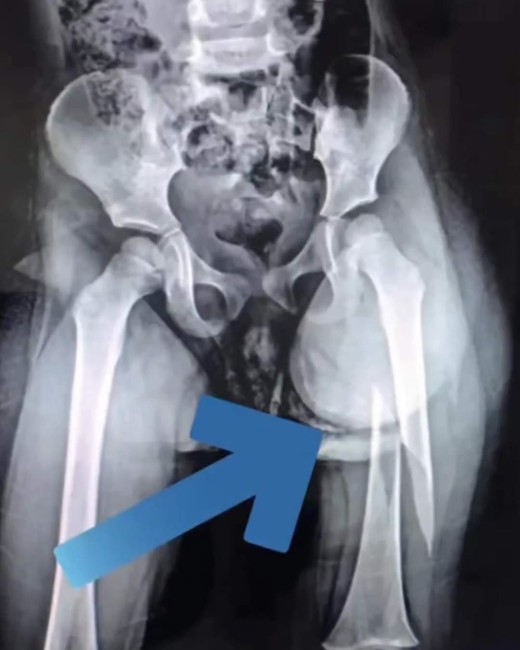

Η Majlinda Dehima είναι η παιδαγωγός του νηπιαγωγείου «Stinet» στα Τίρανα που ξυλοκόπησε βάναυσα ένα 3χρονο κοριτσάκι σπάζοντας της το πόδι.

Στο βίντεο που δόθηκε στη δημοσιότητα, η παιδαγωγός φέρεται απάνθρωπα στην ανήλικη καθώς χτυπάει την μικρή στην πλάτη με έναν χάρακα ενώ είναι ήδη με σπασμένο πόδι.